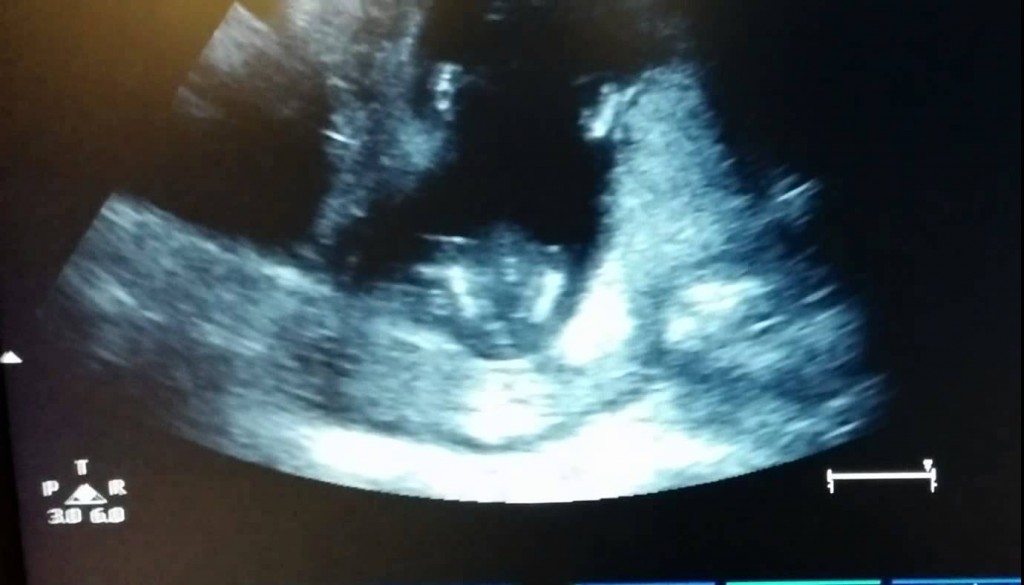

Dat baby’s geen ritme hebben? Zelfs sommige ongeboren baby’s hebben ritme. Kijk maar eens hoe deze foetus mee klapt op de tonen van If you are happy and you know it.